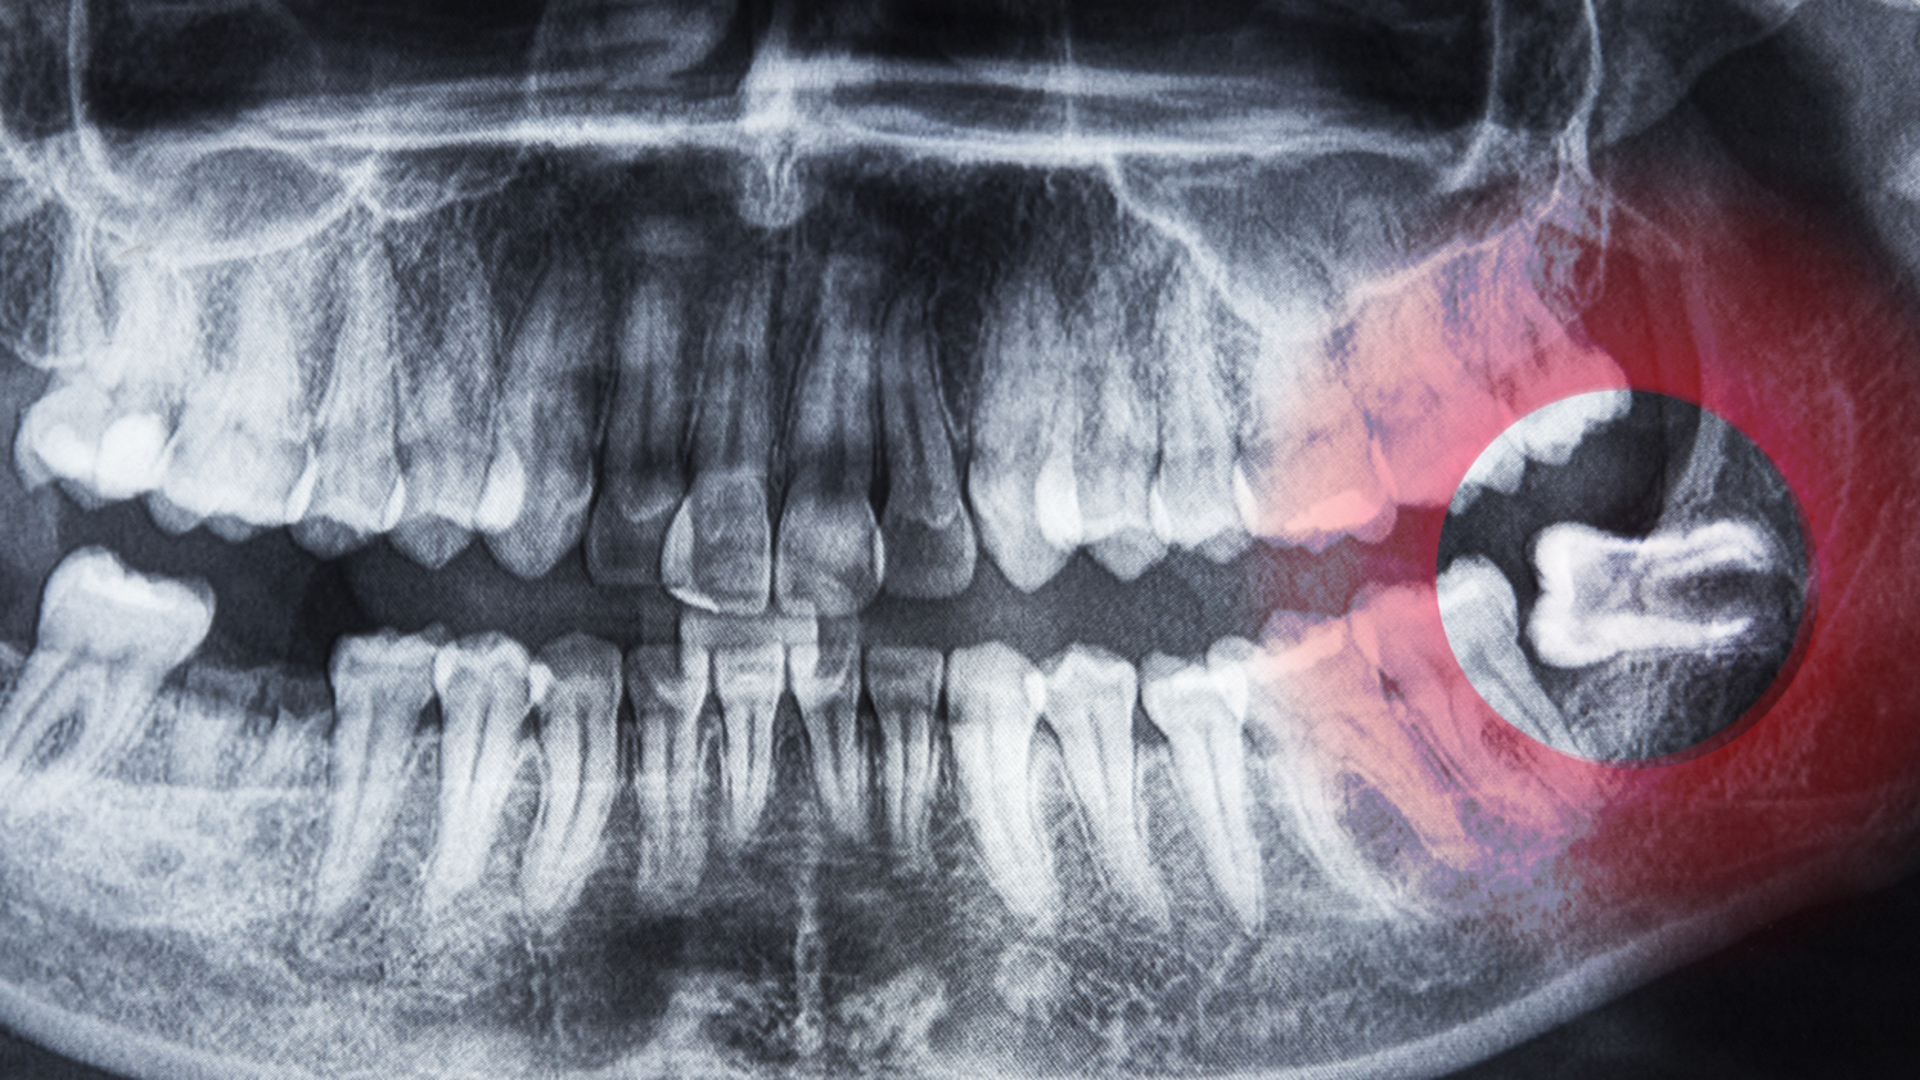

Çoğunlukla zararsız olan bu yapılar, cerrahiyle kolayca alınabilir.YİRMİLİK DİŞLER Geçmişte sert yiyecekleri öğütmek için gerekli olan üçüncü azı dişleri, günümüzde küçülen çeneler nedeniyle çoğu insanda gömülü kalıyor ya da hiç oluşmuyor.

Bu nedenle yirmilik dişler artık işlevsiz kabul ediliyor.

İlginç şekilde, bazı modern toplumlarda bu dişlerin doğuştan eksikliği giderek artıyor.ÜÇÜNCÜ GÖZ KAPAĞI İnsan gözünün iç köşesinde bulunan plica semilunaris, hayvanlardaki üçüncü göz kapağının evrimsel kalıntısıdır.